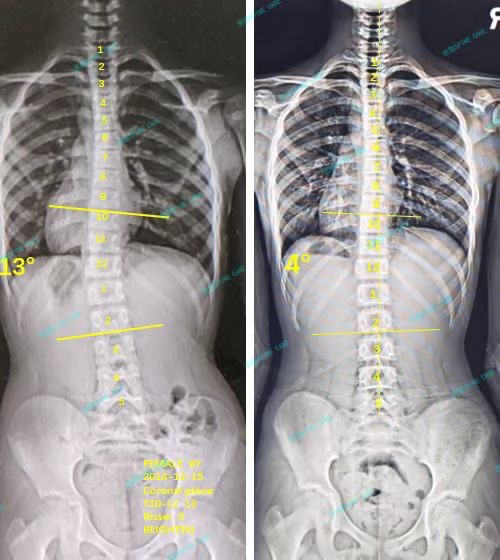

我是朵朵,坚持ZDT训练预防侧弯两年,13度降至4度,角度保持稳定~

案例主人:朵朵 发现侧弯年龄:11岁 侧弯情况:Cobb角度13度

一直到现在已经两年多了,最近一次拍片显示,我的角度已经从最开始的13度降低到了4度,谢谢杨博士,我还会继续坚持做训练,预防侧弯~

Up to now, it has been more than two years. The latest X-ray shows that my scoliosis angle has decreased from the initial 13 degrees to 4 degrees. Thank you, Dr. Yang. I will continue to persist in training to prevent the scoliosis from worsening.